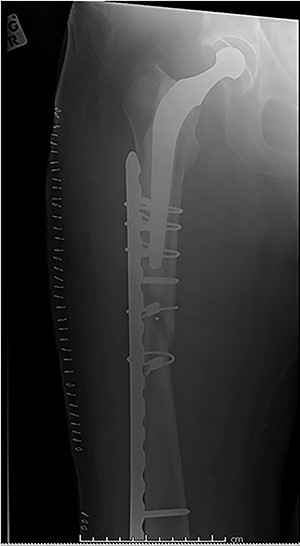

The cases of failure are here examined in more detail. Case 1 (Figs 1 and 2): this active gentleman was paddleboarding off the Llŷn peninsula when he was knocked onto his side by a wave.

Fracture above plate tip following successful union for Case 1.

Clearly, this has occurred following on from successful union. Despite a sound original fixation, the rigid construct has acted as a lever-arm to produce a fracture above the plate tip. In long spiral fracture configurations such as this, antegrade intra-medullary nailing could be considered as the primary treatment modality.